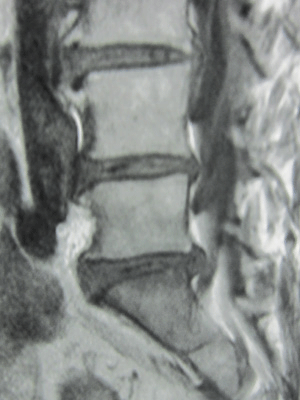

病院でMRIを撮ってもらったところ「椎間板ヘルニアによる坐骨神経痛」と診断された。